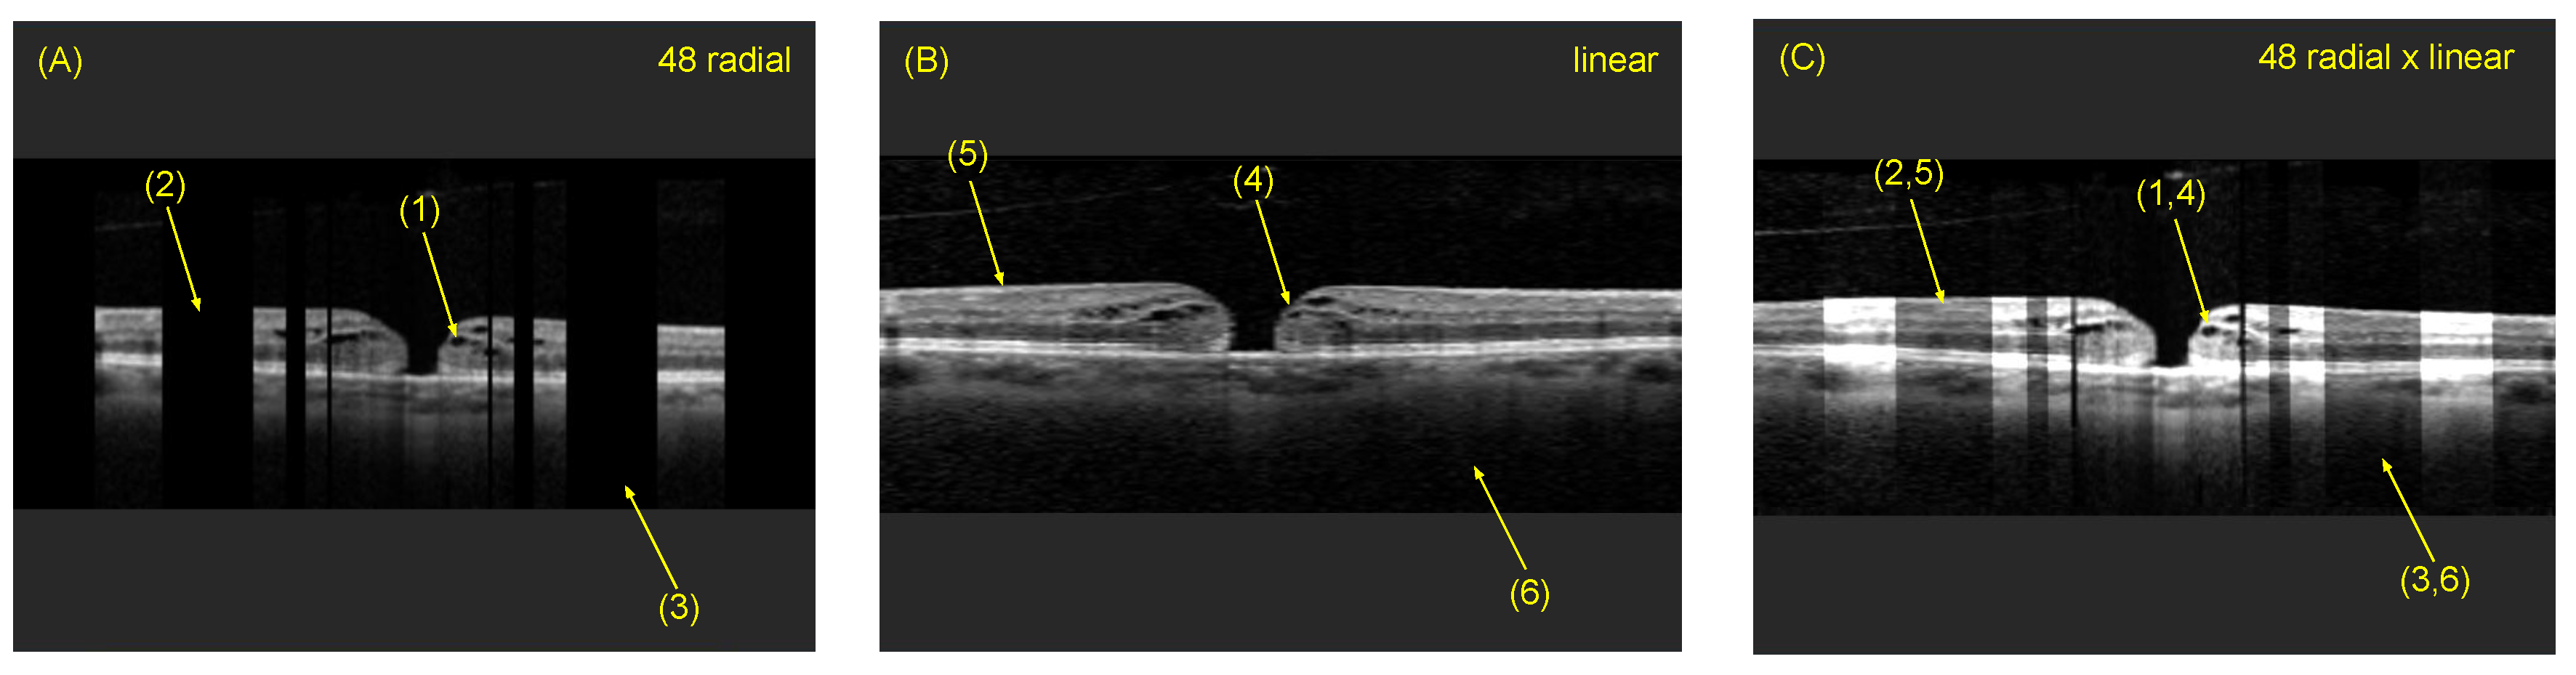

4.3. Comparison of Radial and Fused OCT Reconstruction

4.4. Comparison of Individual B-Scan Slice